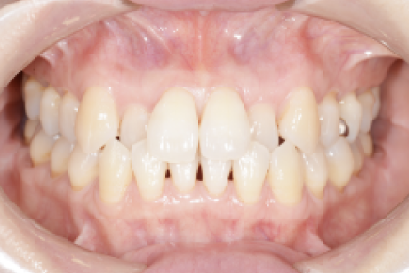

• 症例6

術前

*

術後

年代、性別

40代、女性

職業

会社員

主訴

歯並び相談

部位

インビザラインによる部分矯正

治療期間

6ヶ月

矯正費用

45万円

施術説明

矯正治療を長年希望していましたが、費用的に躊躇していたそうですが、審査の結果インビザラインの部分矯正で起用を抑えて対応できると判断しました。半年の治療期間で希望通りの結果を出す事ができ喜んで頂きました。

副作用・リスク

なし